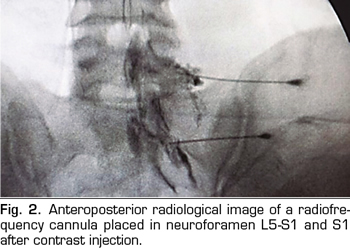

The procedure was performed in the surgical room in ventral decubitus position. A peripheral venous catheter and standard monitoring were placed. The C-shaped arch was used for the location of the DRGs through the anteroposterior, oblique and profile approaches (Figures 1 and 2). A Cosman G4 radiofrequency generator was used. Radiofrequency cannulae number 22 or 20, 10 or 15 cm length respectively, were used, based on the patient’s size, with 1 cm of active tip. The radiofrequency cannula was placed on the anterior-superior side or roof of the selected neuroforamens (Figure 1). In the case of S1, the cannula was placed in the first sacral foramen and the radiofrequency of the nerve root was performed, instead of approaching the dorsal root ganglion through the sacrum, because this is considered excessively invasive. The needle was deepened to an imaginary line located in the middle of the thickness of the sacrum (Figure 2).